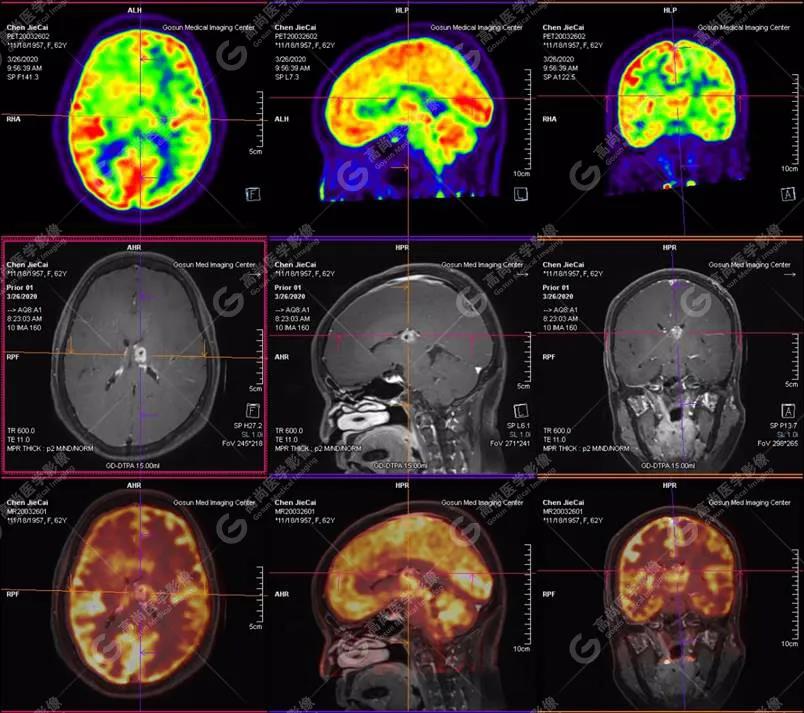

【廣東高尚醫(yī)學(xué)影像】多模態(tài)影像|顱內(nèi)淋巴瘤PET-MR融合顯像1例

影像圖

PET-MR融合診斷

左側(cè)顳葉、頂葉、左側(cè)基底節(jié)區(qū)及胼胝體部多發(fā)結(jié)節(jié)狀高代謝病灶,部分合并囊變、出血,MR平掃+增強(qiáng)示不均勻輕、中度強(qiáng)化,綜合考慮為顱內(nèi)原發(fā)惡性腫瘤,以淋巴瘤可能性大